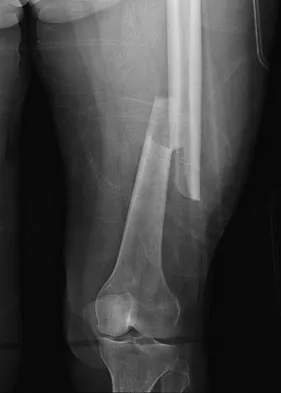

Question 16

Figure 22 shows the radiograph of a 7-year-old boy who underwent retrograde elastic nailing of a femoral shaft fracture. What is the most common problem following this procedure?